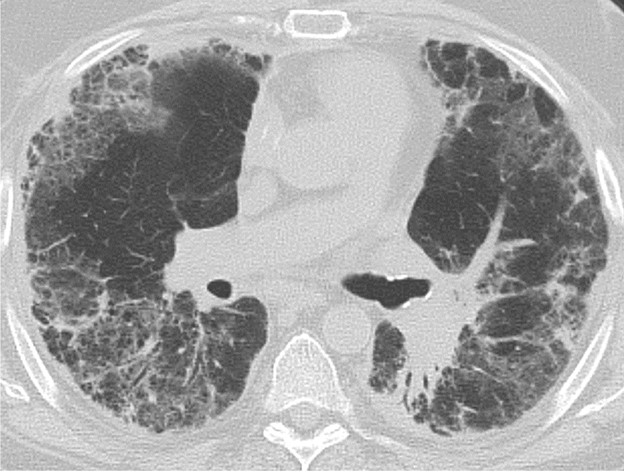

Acute rejection can occur anytime after lung transplant. It consists of two types, acute cellular rejection (ACR) and antibody-mediated rejection (AMR), which can coexist. ACR is the more common of the two types and occurs when recipient T lymphocytes attack donor antigens within the lung allograft. Approximately 35% of lung transplant recipients experience at least one episode of ACR during the 1st year after transplant [2]. During these episodes, patients may be asymptomatic or may present with nonspecific symptoms such as dyspnea and cough. The imaging findings of ACR are nonspecific and include consolidation, ground-glass opacities, and septal-line thickening; as with hyperacute rejection, ACR resembles pulmonary edema. Given its nonspecific clinical and imaging manifestations, ACR requires transbronchial biopsy and tissue analysis for diagnosis. Timely treatment, typically by increased immunosuppression with steroids, is important because ACR is the greatest risk factor for chronic lung allograft dysfunction [4]. Figure 1 shows a patient with biopsy-proven ACR.

Fig. 2—Patient with history of bilateral lung transplant who developed antibody-mediated rejection (AMR), which was diagnosed by transbronchial biopsy and donor-specific antibody blood testing. Chest CT at time of AMR diagnosis shows ground-glass opacities and reticulation in both lungs and small pleural effusions.